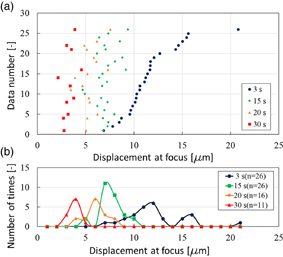

One use for LMI is to measure coagulation size during HIFU treatment. As mentioned, LMI is a method of measuring coagulation size using the change in tissue displacement before and after coagulation at the same position during HIFU ablation. To detect tissue coagulation, a method using cross-correlation between before and after B-mode images during HIFU treatment has been studied. In this method, the coagulated region is estimated by a change in brightness in B-mode images at the same position. Therefore, when monitoring positions were misaligned, the detection of a coagulated area was difficult. In contrast, LMI is based on a change of physical properties of living tissue. Consequently, another use for LMI is therapy evaluation after HIFU treatment. The HIFU beam induces irreversible thermal coagulation in living tissue, and LMI detects an average elastic modulus before and after thermal coagulation in an oscillated area as a tissue displacement. When LMI displacements in normal and coagulated tissue are dramatically different, LMI can assess a treated area in normal tissue using the scanning HIFU transducer operating on low power over a short time without thermal coagulation. When tissue displacement is large, the measured area is normal tissue. In contrast, when tissue displacement is small, the measured area is coagulated tissue. Figure 15(a) shows tissue displacements at focus measured by LMI (n = 26). In this case, the AM frequency was 168 Hz. The HIFU ablation times were 15, 20, and 30 s. The horizontal and vertical axes are displacement at focus and the data number, respectively. Blue, green, orange, and red points represent the displacement at 3 (before coagulation), 15 (beginning of coagulation), 20, and 30 s after the start of HIFU ablation, respectively. The tissue displacements after coagulation tended to decrease compared with those before coagulation. Figure 15(b) shows a histogram of the data in Fig. 15(a). The horizontal and vertical axes are the displacement at the focus and the number of times, respectively. The displacement distribution at 15 s overlaps with that at 3 s. In contrast, the displacement distribution at 30 s does not overlap with that at 3 s. These results show that tissue displacements can be separated by sufficient coagulation. Therefore, LMI has the potential to assess a treated area after HIFU treatment based on the difference in absolute displacements. Currently, HIFU treatment is allowed only for a benign tumor. In contrast, in the case of HIFU treatment for a malignant tumor, it is desired to treat the whole targeted region without leaving tumor behind. Therefore, it is important that a treated area and the surrounding tissue are assessed after HIFU treatment. Our proposed LMI method is expected to be a suitable assessment method.

Fig. 15. (a) Tissue displacement at focus measured by LMI in each sample and (b) a histogram of those data (L = 20 mm, 20 °C).

The LMI displacements in normal and coagulated tissue were significantly different. A treated area in normal tissue can be detected and compared with absolute LMI displacement before and after coagulation. LMI is expected to be used in therapy evaluation after HIFU treatment.